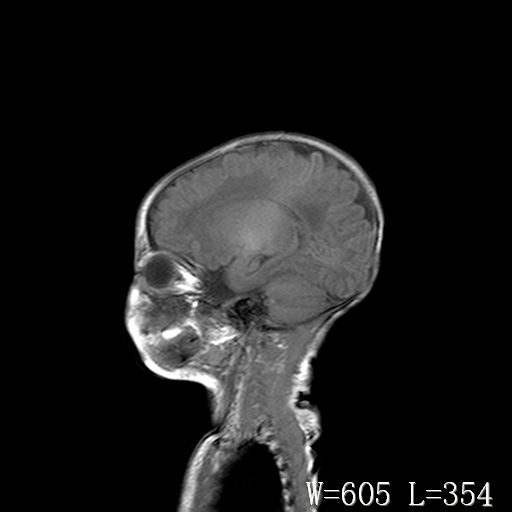

男,4天,发复抽搐1天。

脑干形态欠规则,信号增高,不知怎么解释?

脑干背侧面t1高信号是,新生儿正常已经髓鞘化好的部位